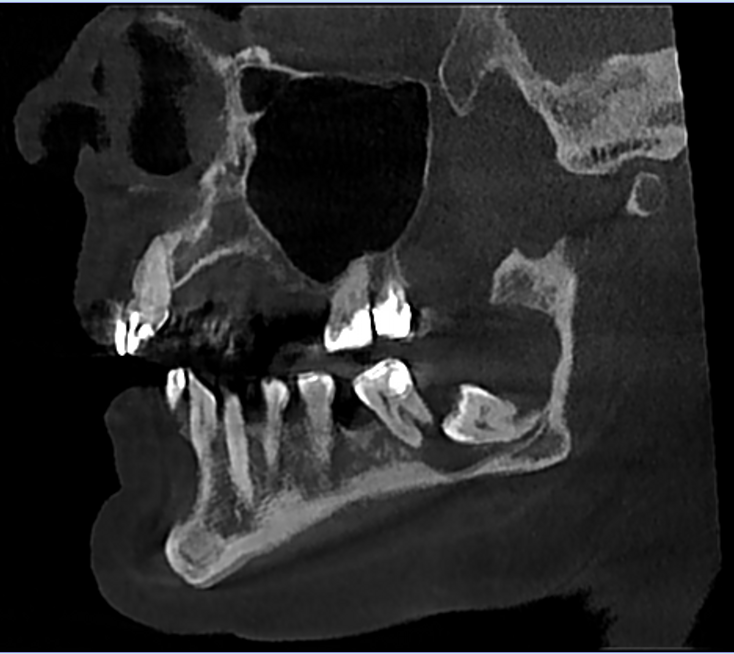

Pacjentka przyjmowała na stałe rywaroksaban i kwas acetylosalicylowy z powodu zakrzepicy żył głębokich kończyn dolnych oraz leki na nadciśnienie tętnicze – walsartan i amlodypinę. W badaniu zewnątrzustnym nie stwierdzono odchyleń od normy. W badaniu wewnątrzustnym stwierdzono chełbotanie wyczuwalne od strony przedsionkowej i językowej po stronie prawej żuchwy. W badaniu CBCT stwierdzono zmianę o charakterze osteolitycznym wielkości 43 mm × 41 mm × 12 mm (w największym wymiarze), która zajmowała prawy trzon, kąt i gałąź żuchwy oraz obejmowała drugi (ząb 47) oraz trzeci ząb trzonowy (ząb 48). Zmiana perforowała blaszkę zbitą od strony przedsionkowej i językowej (ryc. 1). Zaplanowano zabieg w znieczuleniu miejscowym. Dobę przed zabiegiem u pacjentki wdrożono antybiotykoterapię w postaci klindamycyny (300 mg), stosowanej co 8 godzin.

Ryc. 1. Badanie CBCT: a) rekonstrukcja pantomograficzna; b) przekrój poprzeczny; c) przekrój strzałkowy – widoczna zmiana o charakterze osteolizy, związana z zatrzymanym zębem 48 (listopad 2020).